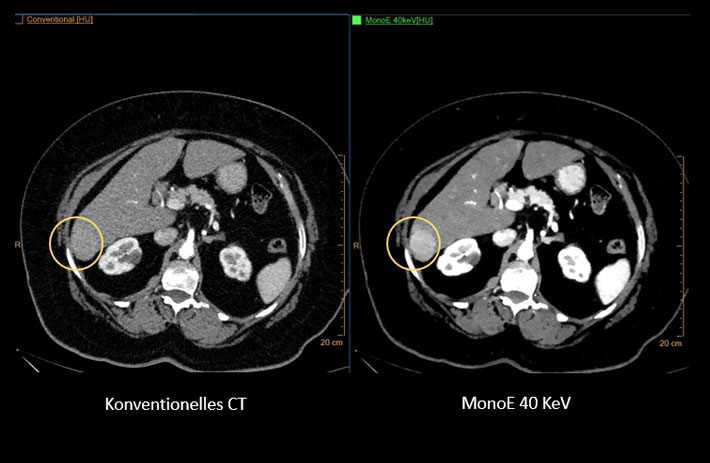

Mit dem Spektral-Detektor-CT werden Spektraldaten automatisch bei jedem Scan erfasst. Die Informationen stehen jederzeit auf der Scankonsole, der CT-Workstation sowie an jedem PACS-Arbeitsplatz zur Verfügung, sodass es nicht notwendig ist, den Patienten erneut zu scannen, bspw. wenn initial zufällige Anomalien festgestellt wurden. Dadurch profitieren Anwender durch eine höhere Diagnosesicherheit und weniger Nachuntersuchungen auf anderen bildgebenden Systemen. Unsere Fallsammlung zeigt, welchen klinischen Mehrwert der Spektral-Detektor-CT in unterschiedlichsten Anwendungsbereichen in der klinischen Routine bringt. Jede Woche gehen neue Fälle live.